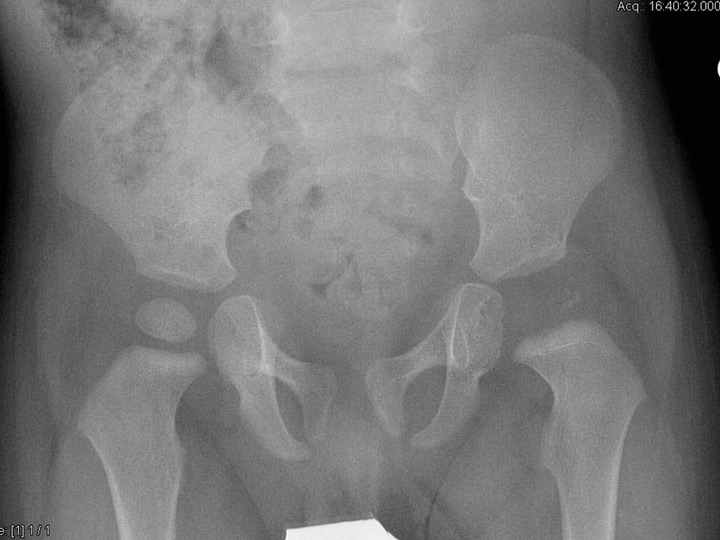

Figure 1

An 8-month-old boy sustained osteoarthritis of the left hip due to Streptococcus pneumoniae. Six months after the infection, the epiphyis had completely disappeared, confirming that children with osteoarticular infection due to S. pyogenesare more likely to have joint involvement, spread of infection into the epiphysis, and thus subsequent disturbed epiphysial growth.